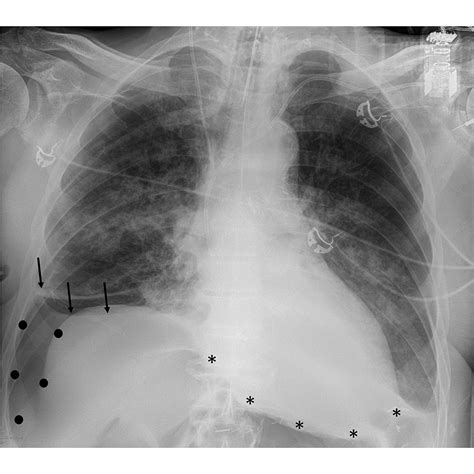

The Deep Sulcus Sign is characterized by an abnormally deep and lucent (dark) costophrenic angle on a supine chest X-ray. Under normal circumstances, the costophrenic angle—the sharp point where the diaphragm meets the ribs—should be relatively shallow. When a pneumothorax occurs in a supine patient, the free air tracks to the most non-dependent part of the pleural space, which, in this position, is the anterior and lateral costophrenic sulcus.

This accumulation of air causes the costophrenic angle to appear hyperlucent and deeper than usual, often extending further inferiorly than the contralateral side. Recognizing this sign is paramount because, in supine radiography, standard signs of pneumothorax—such as the visualization of a visceral pleural line—are frequently absent or obscured, leading to a high rate of missed diagnoses.

While the Deep Sulcus Sign is highly specific for pneumothorax, it is not infallible. Radiologists and emergency physicians must be aware of "mimics" that can simulate the appearance of increased lucency. For instance, overlying skin folds, patient rotation during the X-ray, or differences in soft tissue thickness can sometimes lead to diagnostic errors. Furthermore, the sensitivity of supine radiographs for pneumothorax is generally lower than that of upright films or CT scans.